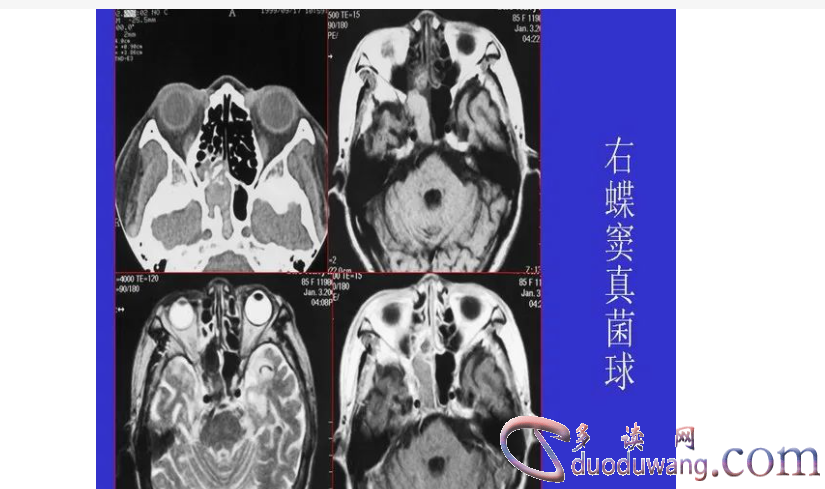

头颅ct是一种无创检查手段,利用x光的双转向摄影和计算机重组技术来制作头颅三维图像。它广泛用于诊断头部和颈部的疾病,如肿瘤、脑血管疾病和副鼻窦炎等。